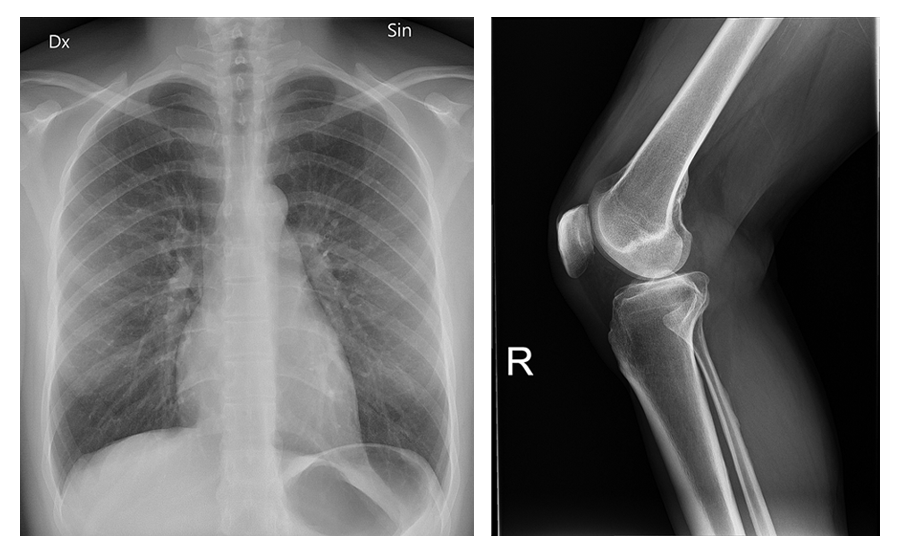

X-ray images are described based on how their opacity versus translucency to X-rays. Radiopaque materials such as bones and metallic implants block x-rays, while radiolucent materials such as air and gas allow X-rays to pass through.

The image below shows a chest X-ray on the left and a leg X-ray on the right. Note how the bones are more white (radiopaque) and the air in the lungs is dark (radiolucent).

An X-ray shows a chest, including ribs; the ribs vertebrae, and other bones are whiter than the dark lung regions. A second X-ray shows bones above and below a knee. The bone outlines are bright white and surrounding tissues are more gray.